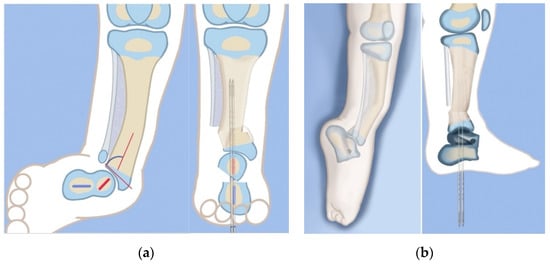

The SHORDT procedure (SHortening Osteotomy Realignment Distal Tibia) was designed by the senior author (D.P.) in 2014 to treat valgus instability of the ankle in patients who have a hypoplastic fibula with a distal fibula physis present [18] (Figure 4). This is commonly found in Paley type 2 FH. The SHORDT procedure involves a shortening and realignment tibial supramalleolar osteotomy to correct ankle valgus and procurvatum malorientation and lengthen the fibula relative to the tibia. This often results in a trapezoidal segment of bone being removed from the tibia and requires taking down the ankle syndesmosis before shortening the distal tibia. By shortening the tibia relative to the fibula, the fibula is effectively lengthened, restoring the buttressing effect of the lateral malleolus against dynamic ankle valgus. This addresses the foot and ankle deformity and instability in Paley type 2 FH and prepares the patient for concomitate or future leg lengthening. The SHORDT procedure does produce an acquired leg length discrepancy by the amount shortened that must be accounted for in future limb equalization.

Figure 4.

Illustrations before (left) and after (right) the SHORDT procedure (SHortening Osteotomy Realignment Distal Tibia) for dynamic valgus deformity of Paley type 2 FH. The main elements are the shortening and varusization of the tibial plafond relative to the fibula which does not change length. This eliminates the valgus instability of the ankle joint.